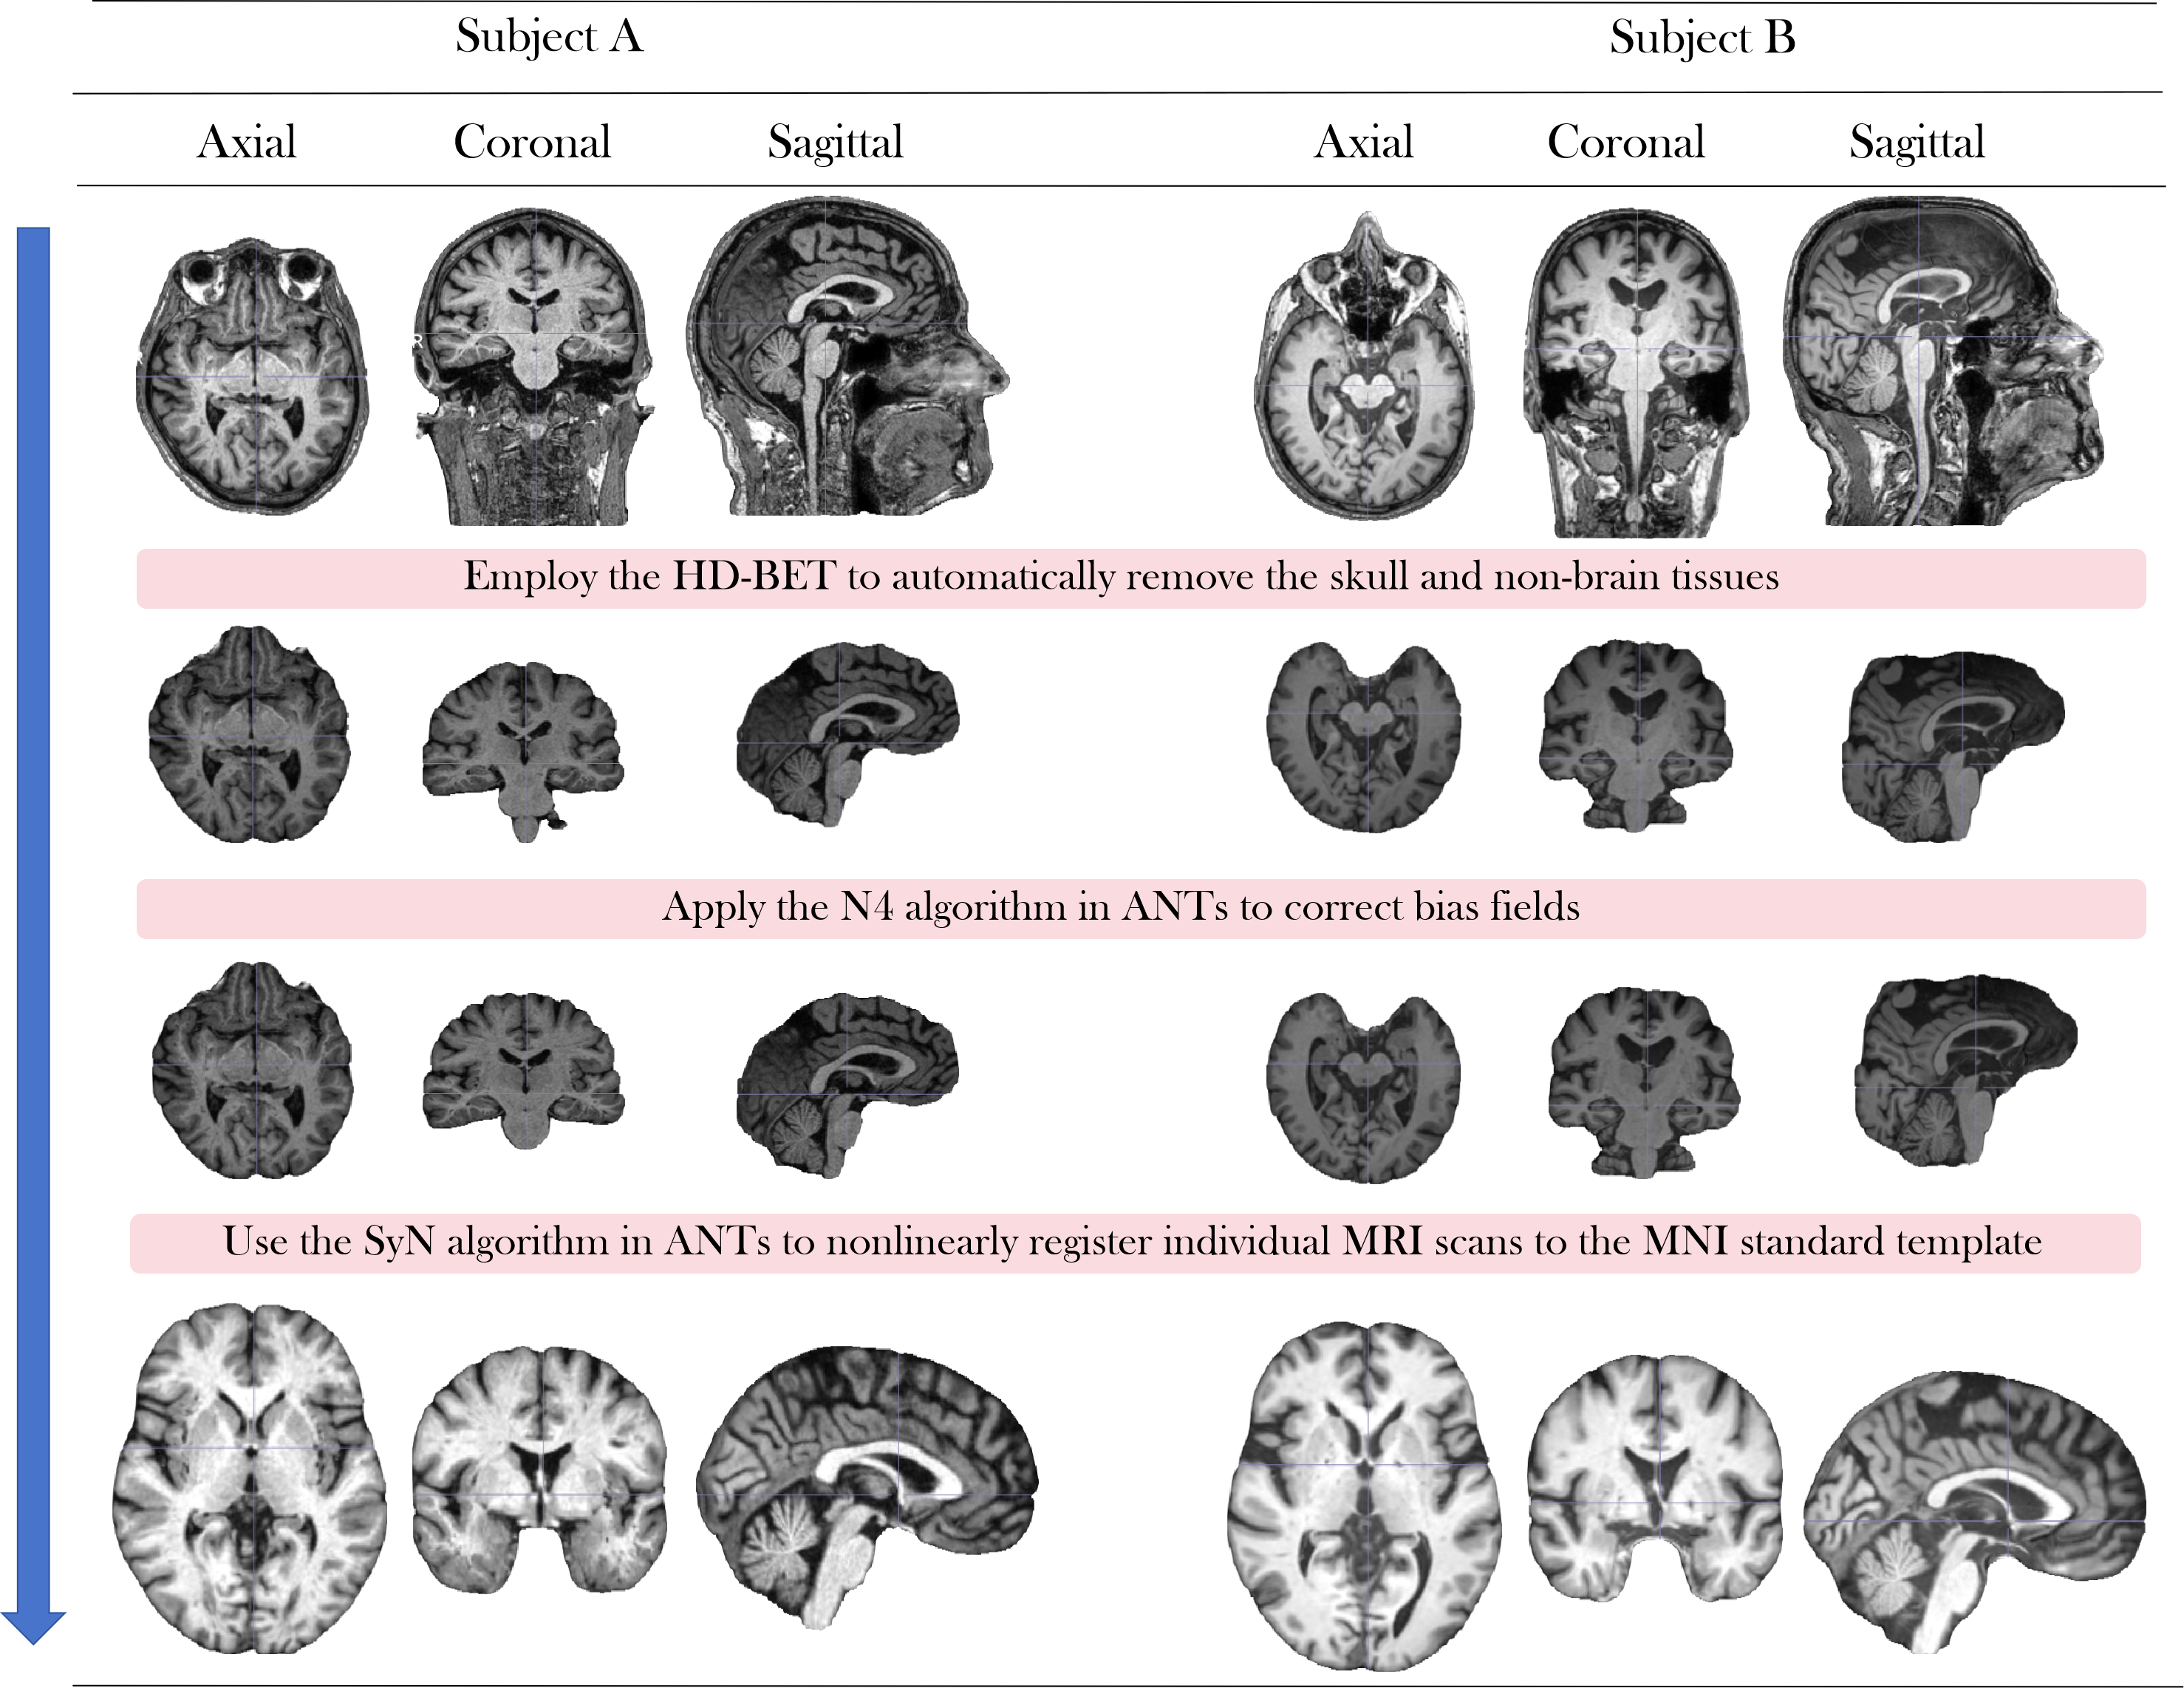

MRI-Processor (see Appendix F) integrates advanced MRI processing tools to standardize raw T1-weighted MRI scans, ensuring data quality and consistency while minimizing adverse effects caused by differences in scanner hardware and individual brain anatomy. It consists of three key steps: (1) Employ the HD-BET (isensee2019automated) to automatically remove the skull and non-brain tissues, isolating the brain parenchyma and facilitating subsequent analysis. (2) Apply the Nonparametric Nonuniform intensity Normalization (N4) algorithm in ANTs (avants2009advanced) to correct bias fields, reducing intensity artifacts caused by magnetic field inhomogeneities during MRI acquisition and improving overall intensity uniformity. (3) Use the Symmetric Normalization (SyN) algorithm in ANTs to nonlinearly register individual MRI scans to the Montreal Neurological Institute (MNI) standard template, enabling consistent cross-subject comparison and group-level analysis.

The MRI-Processor includes three steps: (1) Employ the HD-BET (isensee2019automated) to automatically remove the skull and non-brain tissues, isolating the brain parenchyma and facilitating subsequent analysis. (2) Apply the Nonparametric Nonuniform intensity Normalization (N4) algorithm in ANTs (avants2009advanced) to correct bias fields, reducing intensity artifacts caused by magnetic field inhomogeneities during MRI acquisition and improving overall intensity uniformity. (3) Use the Symmetric Normalization (SyN) algorithm in ANTs to nonlinearly register individual MRI scans to the Montreal Neurological Institute (MNI) standard template, enabling consistent cross-subject comparison and group-level analysis. The flowchart is shown in Fig. 8, and the pseudo code is listed in Algorithm 1.